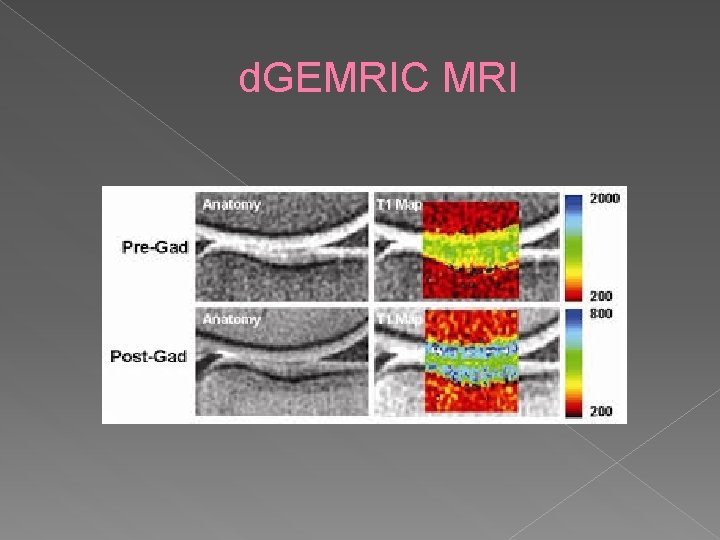

d. GEMRIC MRI Assesses early chondral changes through GAG loss prior to macroscopic cartilage loss • Uses intravenous/intra-articular gadolinium that repels GAGs • With Less GAG in cartilage there is more contrast penetration •

d. GEMRIC MRI